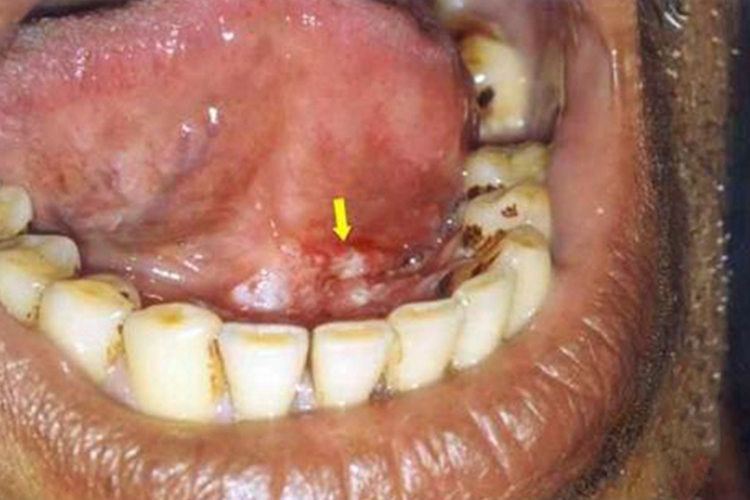

口腔癌

口腔癌初期局限于黏膜内或表皮之中,称为原位癌,随后肿瘤穿过基底膜,侵入周围组织,形成浸润癌,常与周围组织粘连而不能移动,表现为口腔下腭内壁长硬包。

当口腔癌向周围及深部浸润生长时,可以破坏邻近组织器官而发生功能障碍,如面瘫、疼痛、牙松动、颌骨病理性骨折、张口受限等。